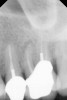

Fig 1. Preoperative radiograph showing apical bone loss.

Figure 1

Clinical procedure: If apical bone loss is present (Figure 1) a collagen/gelatin sponge (eg, Gelfoam®, Pfizer Inc., www.pfizer.com) can be placed apically so that the MTA can be delivered to the desired working length. (Any other surgical resorbable sponge would also work, such as OraPlug® [Salvin Dental Specialties, www.salvin.com], Surgifoam® [Midwest Dental, www.mwdental.com], or Surgispon® [Aegis Lifesciences, www.surgispon.com]). This is done by taking a small piece (2 mm x 2 mm) of the resorbable sponge and pushing it down to and through the root apex with an endodontic file. Once this is done, MTA is packed down the canal with a custom-fitted cone. The clinician can use a rubber stopper on the gutta-percha cone to know the exact length of MTA placed in the apical third (Figure 2). Once the apical third is sealed with 3 mm to 5 mm of MTA, the remaining coronal canal space can be back-filled using a warm gutta-percha technique (Figure 3).